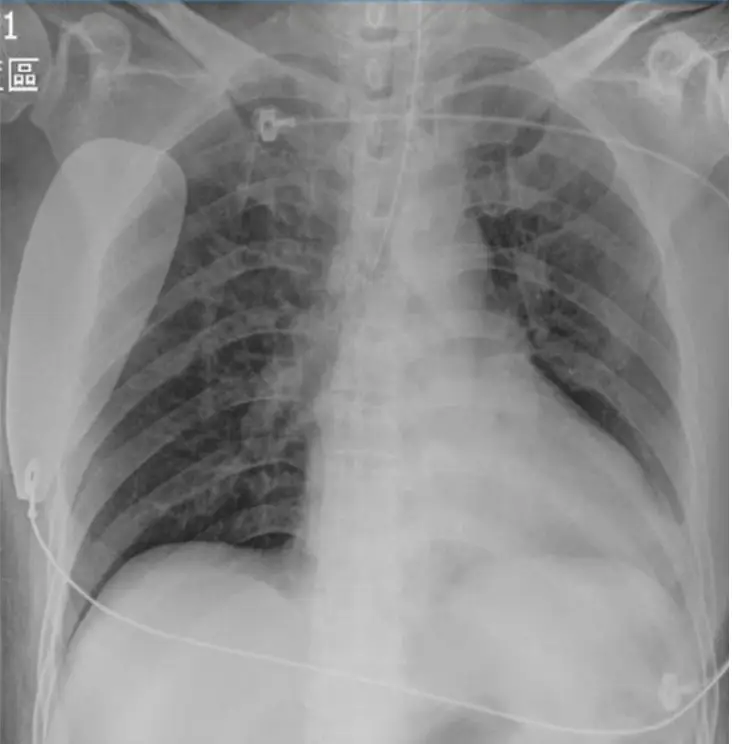

- 胸部X光

- 心影:心臟大小正常,無明顯肺水腫或肺紋理增粗,無感染或肺炎徵象。

- 置管:可見ECMO或監測導線分佈於胸廓。